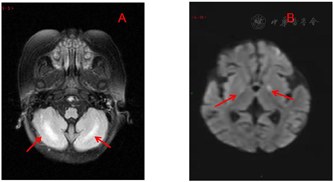

血气分析:pH 6.79,二氧化碳分压15.0 mmHg,氧分压181 mmHg,碳酸氢根2.1 mmol/L,碱剩余-28.9 mmol/L,乳酸0.4 mmol/L,阴离子间隙34.3 mmol/L,钾5.26 mmol/L,钠149 mmol/L,血糖2.1 mmo/L。肝功能未见明显异常。心肌酶及心脏彩超未见异常。头颅MRI示:双侧小脑半球、双侧基底节区见斑片状及小斑片状对称分布异常信号影,边缘不清(图1)。

HMG-CoA合成酶分为胞质型(HMGCS1)和线粒体型(HMGCS2),胞质内表达的HMGCS1主要与胆固醇合成有关,线粒体基质中表达的HMGCS2是酮体合成的限速酶[4]。线粒体HMCSD是一种罕见的酮体生成障碍性代谢紊乱,已报道的病例发病年龄多在3个月~6岁,主要表现包括呕吐、腹泻、肌张力低下、低体温、嗜睡、呼吸暂停甚至昏迷[5,6,7,8,9]。该病易被误诊,患者在无饥饿、感染等诱发之前通常是无症状的;在长时间禁食、感染或者腹泻后,患者迅速出现低血糖、代谢性酸中毒、心肌损害,被误诊为败血症、肾小管酸中毒、扩张性心肌病或心律失常等[2,3,4]。本报道患儿发病前1周添加配方乳及少量辅食,奶量减少,本次感染后出现低血糖、严重酸中毒、休克等,但乳酸正常,且阴离子间隙明显升高,高达34.3 mmol/L,与单纯脓毒性休克表现不符,因此考虑遗传代谢病的可能,奶量减少和感染可能是导致患儿出现低血糖等一系列临床症状的诱发因素。HMCSD患儿由于低血糖及异常代谢产物堆积造成细胞渗透压增高,神经细胞低灌注、神经元受损脑细胞受损,头颅MRI可出现双侧基底节区异常信号以及双侧额、颞、岛叶脑萎缩;多灶性脑白质异常信号和基底神经节损害是该病常见的神经影像学异常[11,12],与本例患儿头颅磁共振表现相符。